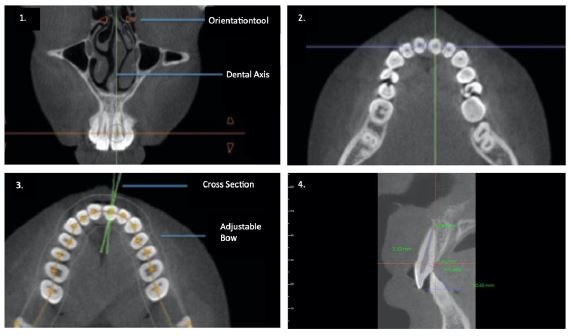

The teeth were grouped into seven categories: central incisors (1), lateral incisors (2), canines (3), first premolars (4), second premolars (5), first molars (6), and second molars (7). The buccal and lingual sides of each tooth (7-7) were measured individually, and the measurements were grouped by upper and lower jaw. To measure a dehiscence, the tooth was positioned vertically at a 90° angle to the horizontal plane, which was set as the lower border of the examination screen. The distance between the cemento-enamel junction and the crestal alveolar bone was measured on the lingual and buccal side, with a maximum slice thickness of 0.1 mm. The measuring points were chosen at the center of the tooth, which was half the horizontal distance between the widest part of the tooth and the apex, connecting the shortest distance between the CEJ and the alveolar crest, parallel to the tooth-axis. An example measurement can be seen in (Figure 1). A dehiscence was defined as being >2 mm, with further differentiation into those >2 mm and those >3 mm. The measurements classified as greater than 2 mm also included measurements greater than 3 mm.

Figure 1: Tooth orientation in four planes: First the transversal plane was used for orientation (1.1), followed by rough alignment in the horizontal plane (1.2) and fine alignment in the horizontal plane (1.3). The boundaries between the enamel and cementum, as well as those between the crestal bone and surrounding tissues, are delineated. Additionally the angulation to the occlusal plane was measured (1.4).